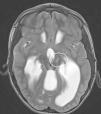

Materials and methodsEight paediatric patients met strict criteria for IND and were enrolled in this study. Electroencephalography (EEG), video electroencephalography (VEEG) and magnetic resonance imaging (MRI) were performed in all patients prior to surgery. Irreducible neuroagressive symptom was approached by lesional therapy based on most described targets for this disorder and assessed by the Overt Aggression Scale (OAS) pre-operatively and 6 months following surgery, using Wilcoxon test for statistical analysis.

Results and conclusionsThe average patient age was 13 years 2 months. 7 of the 8 patients enrolled had intellectual disabilities, 1 patient suffered neurologic sequelae referable to Dandy–Walker syndrome and 7 patients had no preoperative anatomical alterations. Following surgery, patients with IND noted improvement in their OAS. On average, the OAS improved by 39.29% (p=.0156), a figure similar in comparison to studies assessing treatment of IND in adult patients. The most satisfactory results were achieved in patients whose ablative therapy involved the Amygdala in their targets. There were no deaths or permanent neurological deficits attributable to procedure. To the author's knowledge, this is the largest series described in the literature for paediatric patients with IND treated with lesional stereotactic therapy.